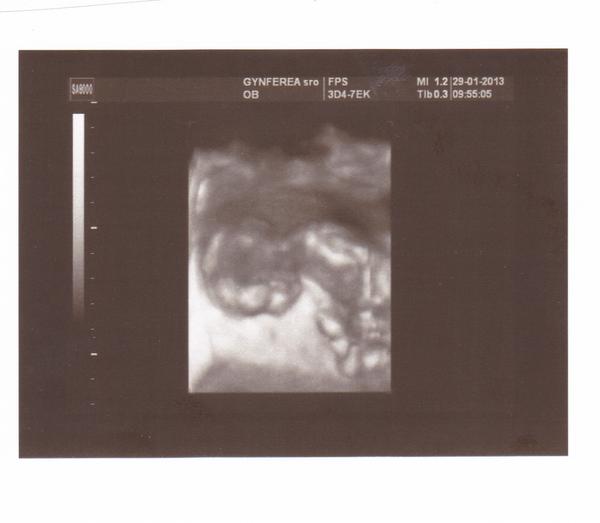

@lylkatomaskova Svagrina bola na zaciatku 12. tt a na foto krasne vidiet aj rucicky a nozicky, babo vyzera ako taky medvedik 🙂

@lylkatomaskova toto je fotka z 12.týždňa a určite sa oplatí 😉

@lylkatomaskova ahoj,urcite sa to oplati,ak ho pan doktor dobre odfoti 🙂 vidiet rucicky,nozicky,dokonca co mam videozaznam zo sona,vidiet detailne aj prstiky na nozicke...je to uzasne 🙂